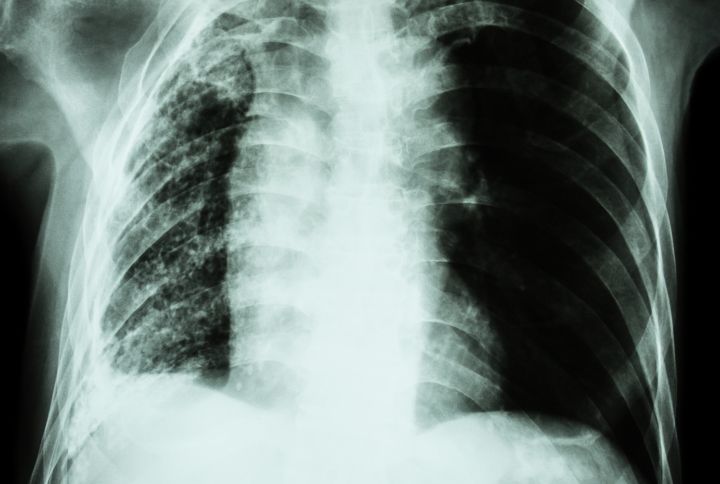

L’atélectasie du poumon n’étant pas toujours symptomatique si la zone affectée est très réduite, la radiographie du thorax est l’examen de choix pour diagnostiquer le trouble. Elle permet de détecter si une zone pulmonaire est sans air. À l’image, cela se traduit par une opacité révélatrice du poumon rétracté. Si la radiographie démontre l’existence d’une atélectasie, un scanner du thorax peut être prescrit pour avoir des images plus précises. Enfin, dans les cas les plus sévères, une bronchoscopie est nécessaire. Cet examen endoscopique, réalisé grâce à un bronchoscope (tube flexible souple muni d’une caméra et d’une pince), permet de visualiser les bronches, la trachée et de faire des prélèvements (biopsie).

Le terme médical "bandes d’atélectasie" désigne les zones pulmonaires opaques, visibles sur les images radiographiques. Elles correspondent aux zones pulmonaires affaissées causées par l'atélectasie.